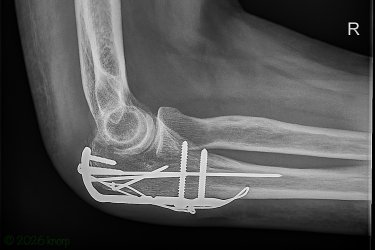

Broke my right elbow (olecranon fracture), badly bruised my forearm and hand in the 'act', but the camera and lens (± 1,5 kg) both survived unscathed !

This is what it took to put it back together, pretty amazing ...

OMG Bart. thats a hell of a lot of nails, screws and special metalpieces !!!